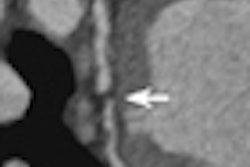

A 57-year-old man with vascular ring, "double aortic arch," huge Kommerell's diverticulum, and aneurysm of the descending aorta. Dysphagia and increasing diameter of the diverticulum can be seen. Images courtesy of Dr. Michael Hübler.Despite these concerns, the future of imaging in GUCH looks set to rapidly evolve, and the use of MRI for diagnostic purposes is likely to increase. Also, MRI may be used as a screening tool to examine the status of relocated coronaries (e.g., after arterial switch or the Ross procedure), and it may replace some invasive catheter-based diagnostic investigations. The use of MRI to document the effects of congenital cardiac diseases and the therapeutic maneuvers on development of the brain is poised for growth, according to Hübler. It will be interesting to see if MR-based interventional procedures can be developed further, particularly to see if flow phenomenon and computerized models can be developed to achieve the best hemodynamic results, he added.